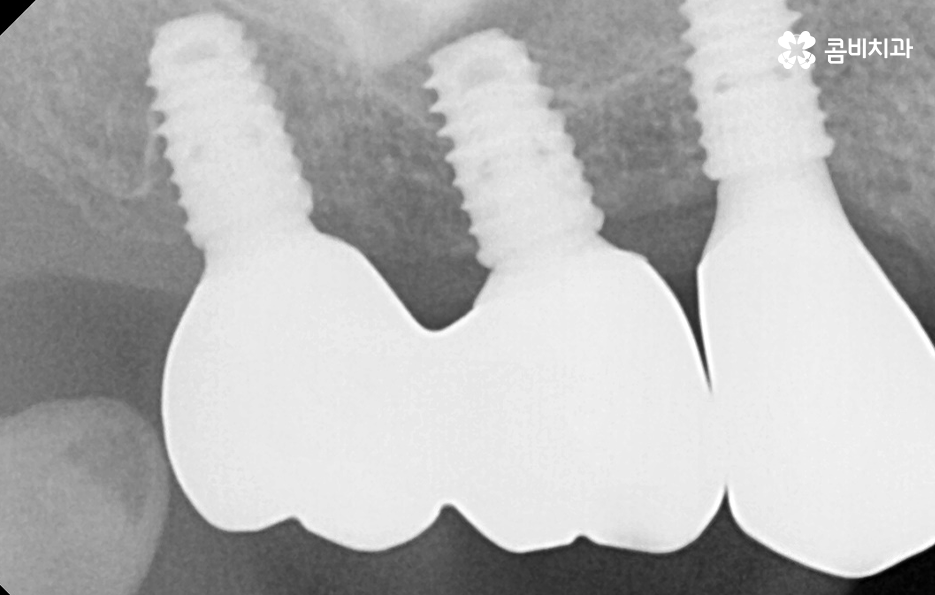

우리가 보편적으로 생각하게 되는 임플란트 치료기간의 경우 치아 하나를 상실하고 임플란트를 1:1로 치료할 때 예상 기간에 대해서 고려하게 되는 경우가 기본적인 접근 방법이라면 실질적으로 치과에서 임플란트를 하게 되는 연령대를 보더라도 보통 50대에서 60대 이후에 치아를 상실하게 되는 환자분들이 급증하기 때문에 위 사진의 사례처럼 여러 치아를 상실하고 임플란트를 식립하게 되는 경우도 많을 거예요